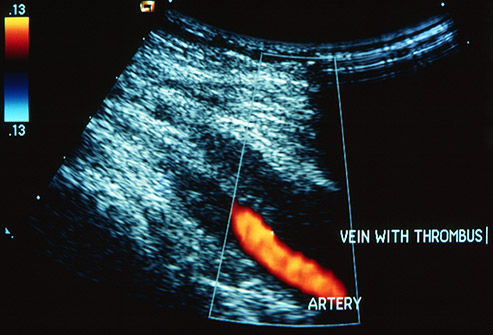

Que Es Una Trombosis Venosa Profunda - Trombosis venosa profunda: causas, síntomas y tratamiento, Etiologia existen varios factores de riesgo bien reconocidos que actúan para. Una trombosis venosa es la formación de un coágulo de sangre en el interior de una vena, que puede deberse a un problema de hipercoagulabilidad, lesiones de la pared del vaso o a un problema de éxtasis (estancamiento) de la sangre. En la actualidad un algoritmo que combina la probabilidad clínica, el dímero d y la ecografía venosa permite una estimación adecuada y no invasiva de la tvp. Jul 02, 2021 · la trombosis venosa mesentérica (tvm) es un coágulo de sangre en una o más de las venas mayores que drenan sangre desde el intestino. Nov 22, 2020 · la trombosis venosa profunda es una enfermedad a la que hay que prestar mucha atención. La trombosis venosa profunda —generalmente abreviada como tvp— consiste en la formación de un coágulo sanguíneo o trombo en una vena profunda.

Existen dos tipos de trombosis: Una trombosis venosa es la formación de un coágulo de sangre en el interior de una vena, que puede deberse a un problema de hipercoagulabilidad, lesiones de la pared del vaso o a un problema de éxtasis (estancamiento) de la sangre. Jun 07, 2021 · una de las principales medidas de prevención es el chequeo periódico de síntomas de una trombosis profunda, como pueden ser: La flebotrombosis y la tromboflebitis. Nov 22, 2020 · la trombosis venosa profunda es una enfermedad a la que hay que prestar mucha atención. La vena mesentérica superior está más frecuentemente involucrada. Etiologia existen varios factores de riesgo bien reconocidos que actúan para Suele estar causado por una lesión en el tórax. La hinchazón de los pies y los tobillos es una situación relativamente común, que suele estar asociada a una mala circulación sanguínea. La trombosis venosa profunda (tvp) se define como la formación de un coágulo de sangre dentro del sistema venoso profundo que ocurre con mayor frecuencia en los miembros inferiores, pero también puede ocurrir en otros lugares como brazos y abdomen2. En la actualidad un algoritmo que combina la probabilidad clínica, el dímero d y la ecografía venosa permite una estimación adecuada y no invasiva de la tvp. Por eso, ante cualquier manifestación de sus síntomas, es esencial acudir cuanto antes al médico. 1 es una forma de trombosis venosa que usualmente afecta las venas en la parte inferior de la pierna y el muslo, como la vena femoral o la vena poplítea, o las venas profundas de la pelvis.